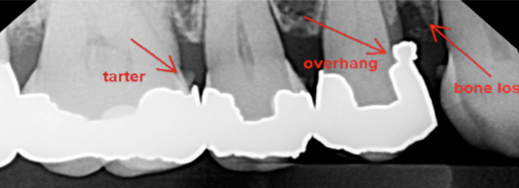

There is a cuff or collar of gum around every tooth we call a “pocket” and this forms a hiding place making it difficult to clean. The bacteria (plaque) irritates the soft gums causing inflammation. This inflammation slowly but surely eats away the bone. Over time this means the grip for the teeth is lost and the teeth get loose eventually falling out or needing extraction.

There are many factors that contribute to this process and we will look at these in following articles, including: Teeth that have tipped and tilted into the spaces of teeth that have been extracted and not replaced.

Poorly fitting fillings and restorations where food and bacteria may catch between them.

First the problem must be identified and diagnosed. Your dentist can assess the degree of bone loss and depth of pockets around your teeth. They may use X-rays to assess the current levels of bone and keep these as a record to compare back to at a later date. Identifying contributory factors and correcting these will be an important part of the treatment. But removal of the bacteria, again and again and again is the mainstay of controlling your gum disease. This is a joint exercise between you, your dentist and your hygienist.